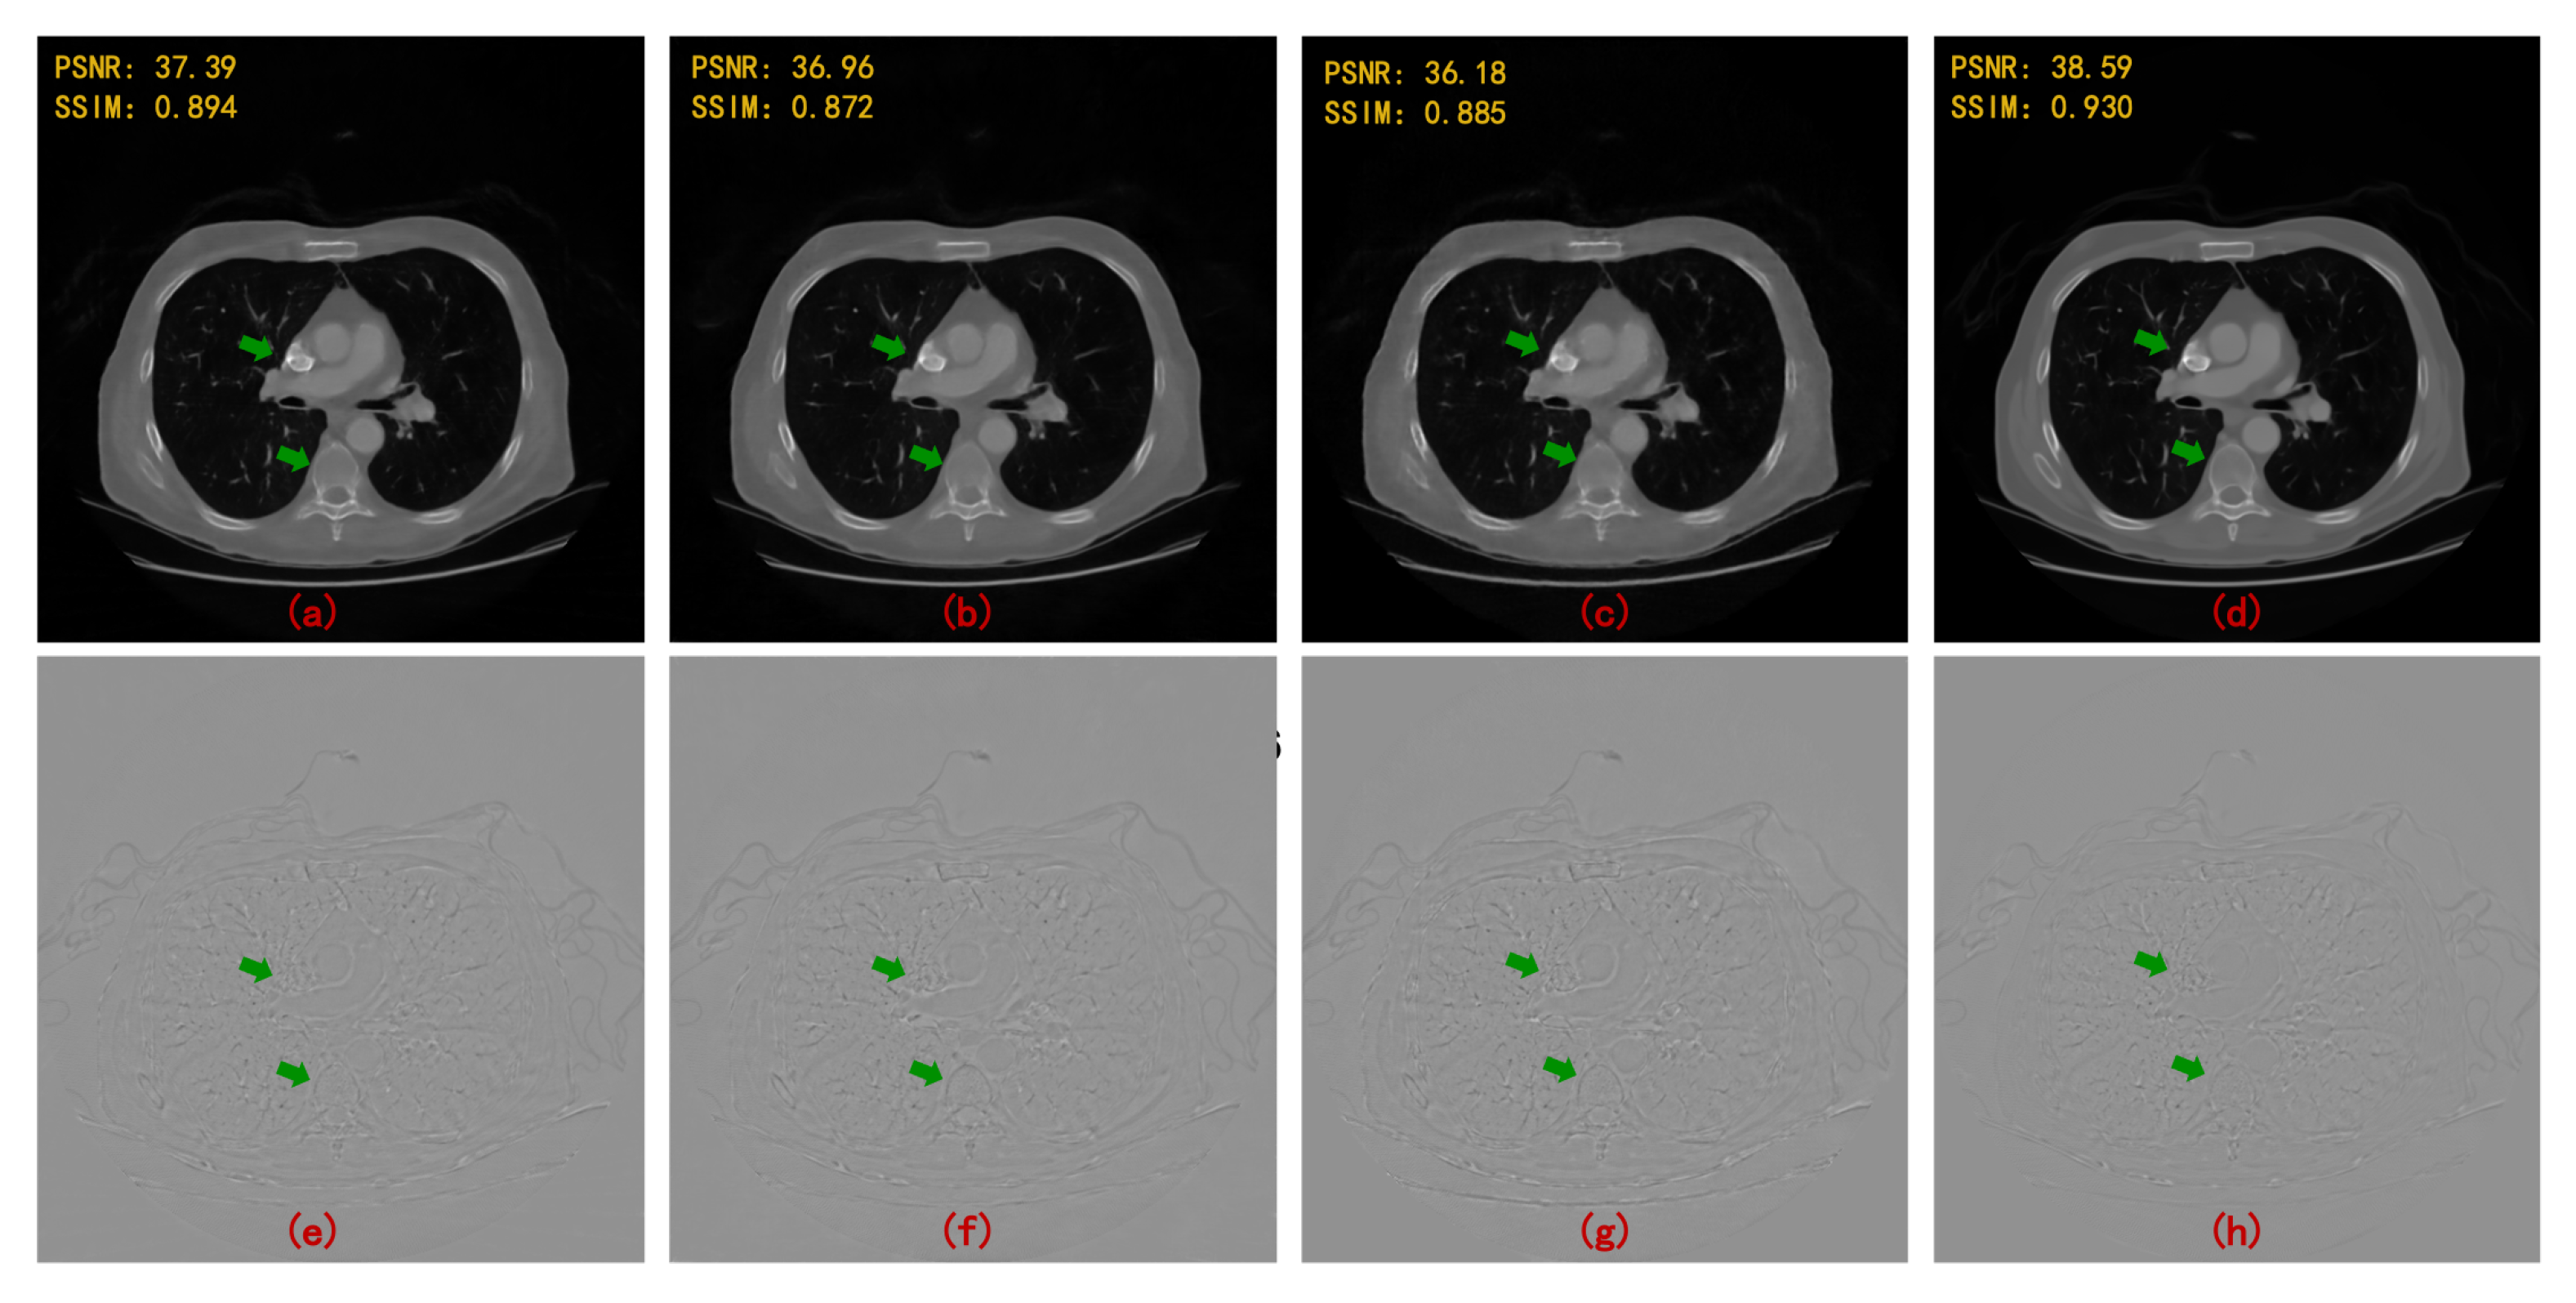

- On the basis of single domain restoration, a hybrid domain reconstruction model for sparse-view CT is proposed, which consists of a projection completion module in radon domain and an image restoration module in image domain. Wavelet domains of projection data and image data are embedded in two modules respectively to better extract spatial features and recover texture details. Moreover, the proposed model is end-to-end learning through the differentiable FBP operator.

- Multi-level wavelet packet decomposition is utilized to replace the pooling operator and enlarge the effective receptive field. Experimental results have shown that a multi-resolution network with a multi-level wavelet transform can effectively suppress globally distributed streaking artifacts.

- A deep residual learning framework is proposed to learn artifacts. Once the artifacts are estimated, an artifact-free image can be obtained by subtracting the estimated results.